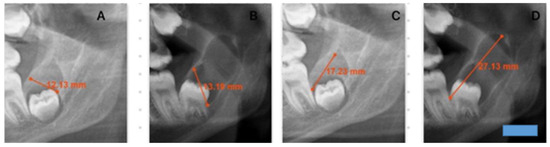

Background: Dens invaginatus is a rare developmental tooth anomaly that can occur in permanent, primary, and supernumerary teeth, with a tendency to affect the maxillary second incisors. It develops during odontogenesis due to the invagination of the enamel organ into the dental papilla. [...] Read more.

Background: Dens invaginatus is a rare developmental tooth anomaly that can occur in permanent, primary, and supernumerary teeth, with a tendency to affect the maxillary second incisors. It develops during odontogenesis due to the invagination of the enamel organ into the dental papilla. Methods: This study describes the endodontic management of a 24-year-old patient with a type IIIb invaginated tooth in the mandibular second molar. Clinical examination revealed no response to thermal and electrical stimuli, no response to vertical and horizontal percussion, and no pathological mobility. The depth of the gingival pocket was 8 mm. Root canal therapy was performed over three sessions. The patient remained asymptomatic during the treatment and follow-up visits. Results: Radiographs at 4-, 6-, and 9-month post-treatment showed healing of the periapical lesion. Conclusions: Due to the complex canal anatomy of invaginated teeth, confirming the diagnosis with cone-beam computed tomography (CBCT) is essential. Treating invaginated teeth presents significant challenges for clinicians, requiring a thorough understanding of the dental anatomical variability, advanced manual skills, and the use of specialized equipment. Full article

Show Figures

Figure 1